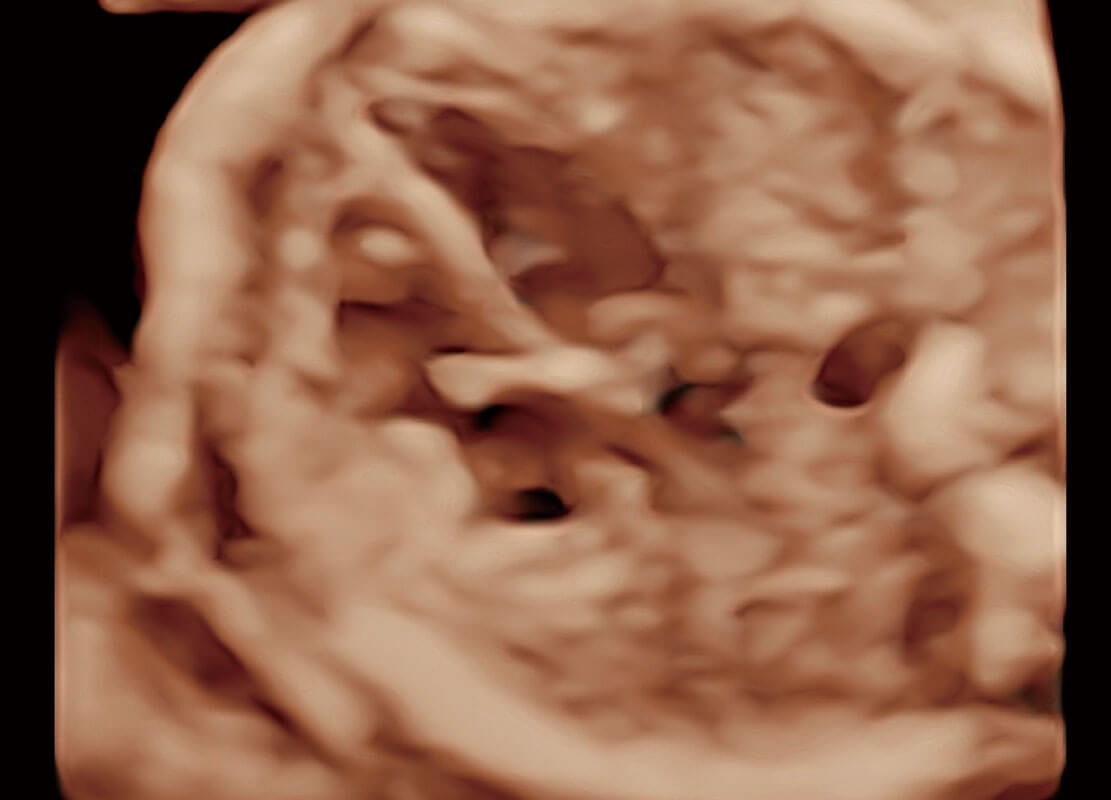

P60在胎儿早孕期超声筛查中为您带来优异的图像质量。

早孕-胎心

高分辨率容积成像-早孕胎儿